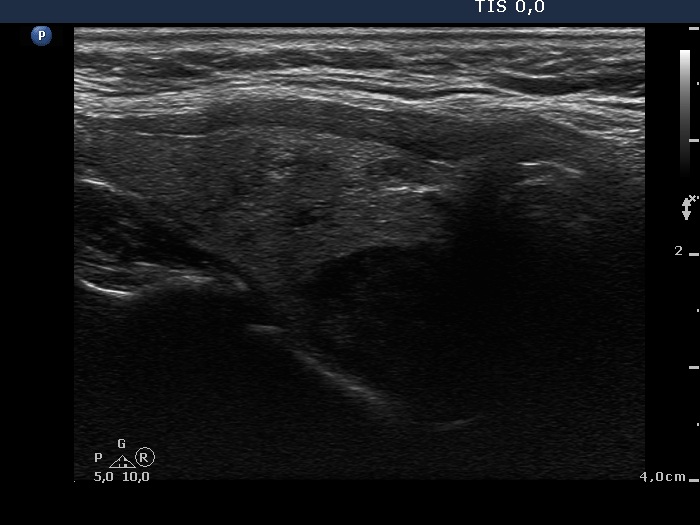

Ultrasonography: The thyroid was echonormal and contained multiple inhomogeneous, hyperechogenic nodules. There was a hypoechogenic lesion in the dorsal part or dorsal to the lower pole of the right lobe.